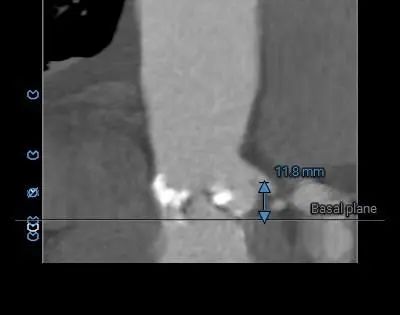

Type 1型二叶式主动脉瓣,右无融合,重度钙化,钙化分布不均匀,无窦和左窦瓣叶钙化较重呈长条块状,右冠窦内钙化向左室流出道衍生,无窦和右窦瓣叶对合缘处存在钙化嵴,左窦和右窦瓣叶对合缘处存在局部钙化黏连,瓣叶对合缘处存在增厚及钙化粘连。

瓦氏窦内径尚可,窦管交界内径尚可、升主动脉内径可,左室腔内径尚可、心室壁增厚,左室流出道呈敞口形态。

考虑右侧股动脉为主入路,左侧为辅助入路。右冠窦内钙化向左室流出道衍生,左室流出道呈敞口形态,非横位心,弓部存在少量散在钙化,预估输送器过弓与跨瓣顺利。瓣叶冗长,CT提示右冠脉显影不佳,建议术前行冠脉造影进一步评估冠脉风险。外周走行可见多处迂曲,需注意小心通过。由于Type1型二叶式主动脉瓣伴瓣叶长条块状重度钙化,瓣口限制明显,手术预装AV26备AV23瓣膜,根据20mm球囊预扩结果选择瓣膜型号,计划瓣膜释放定位深度接近瓣环。